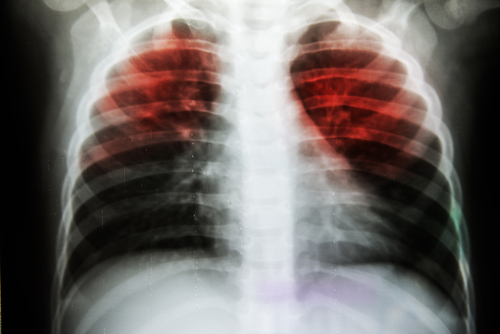

Researchers have developed a new treatment that could be used to treat hundreds of thousands of patients with tuberculosis (TB).

The study showed that the treatment, which patients will take using an inhaler, works by reducing the bacteria in the lungs causing tuberculosis while also helping the patient's immune system to fight the disease. "Many cases of TB are now becoming resistant to existing antibiotics. This new treatment could be used alongside antibiotics to treat drug-resistant TB and also possibly reduce the rate of antibiotic resistance resulting from conventional antibiotic treatments," said Sally-Ann Cryan, Associate Professor at the Royal College of Surgeons in Ireland (RCSI).

TB is one of the top 10 causes of death worldwide. Ten million people fell ill with TB and 1.6 million died from the disease in 2017, according to the World Health Organization (WHO). For the study, the team used a spray-drying process and packaged all trans-Retinoic acid (ATRA) solution -- a derivative of Vitamin A -- within safe-for-consumption particles that are small enough to use in an inhaler.

The findings, published in the European Journal of Pharmaceutics and Biopharmaceutics, demonstrated that these particles efficiently delivered the treatment and significantly reduced TB-causing bacteria and associated lung damage.